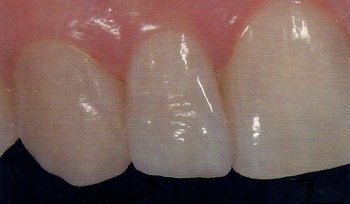

After

Dental fillings are a common and widely recommended treatment and the demand in metal-free restorations has increased enormously in recent years in the dental community as for the general public. Depending on the extent of the tooth damage by decay, fracture or wear and in any case which requires a strictly conservative approach, composite resins fillings became a solution to build up or re-shape the tooth offering an excellent outcome. Beyond the choice of material itself, understanding and mastering the adhesive technique is also important.